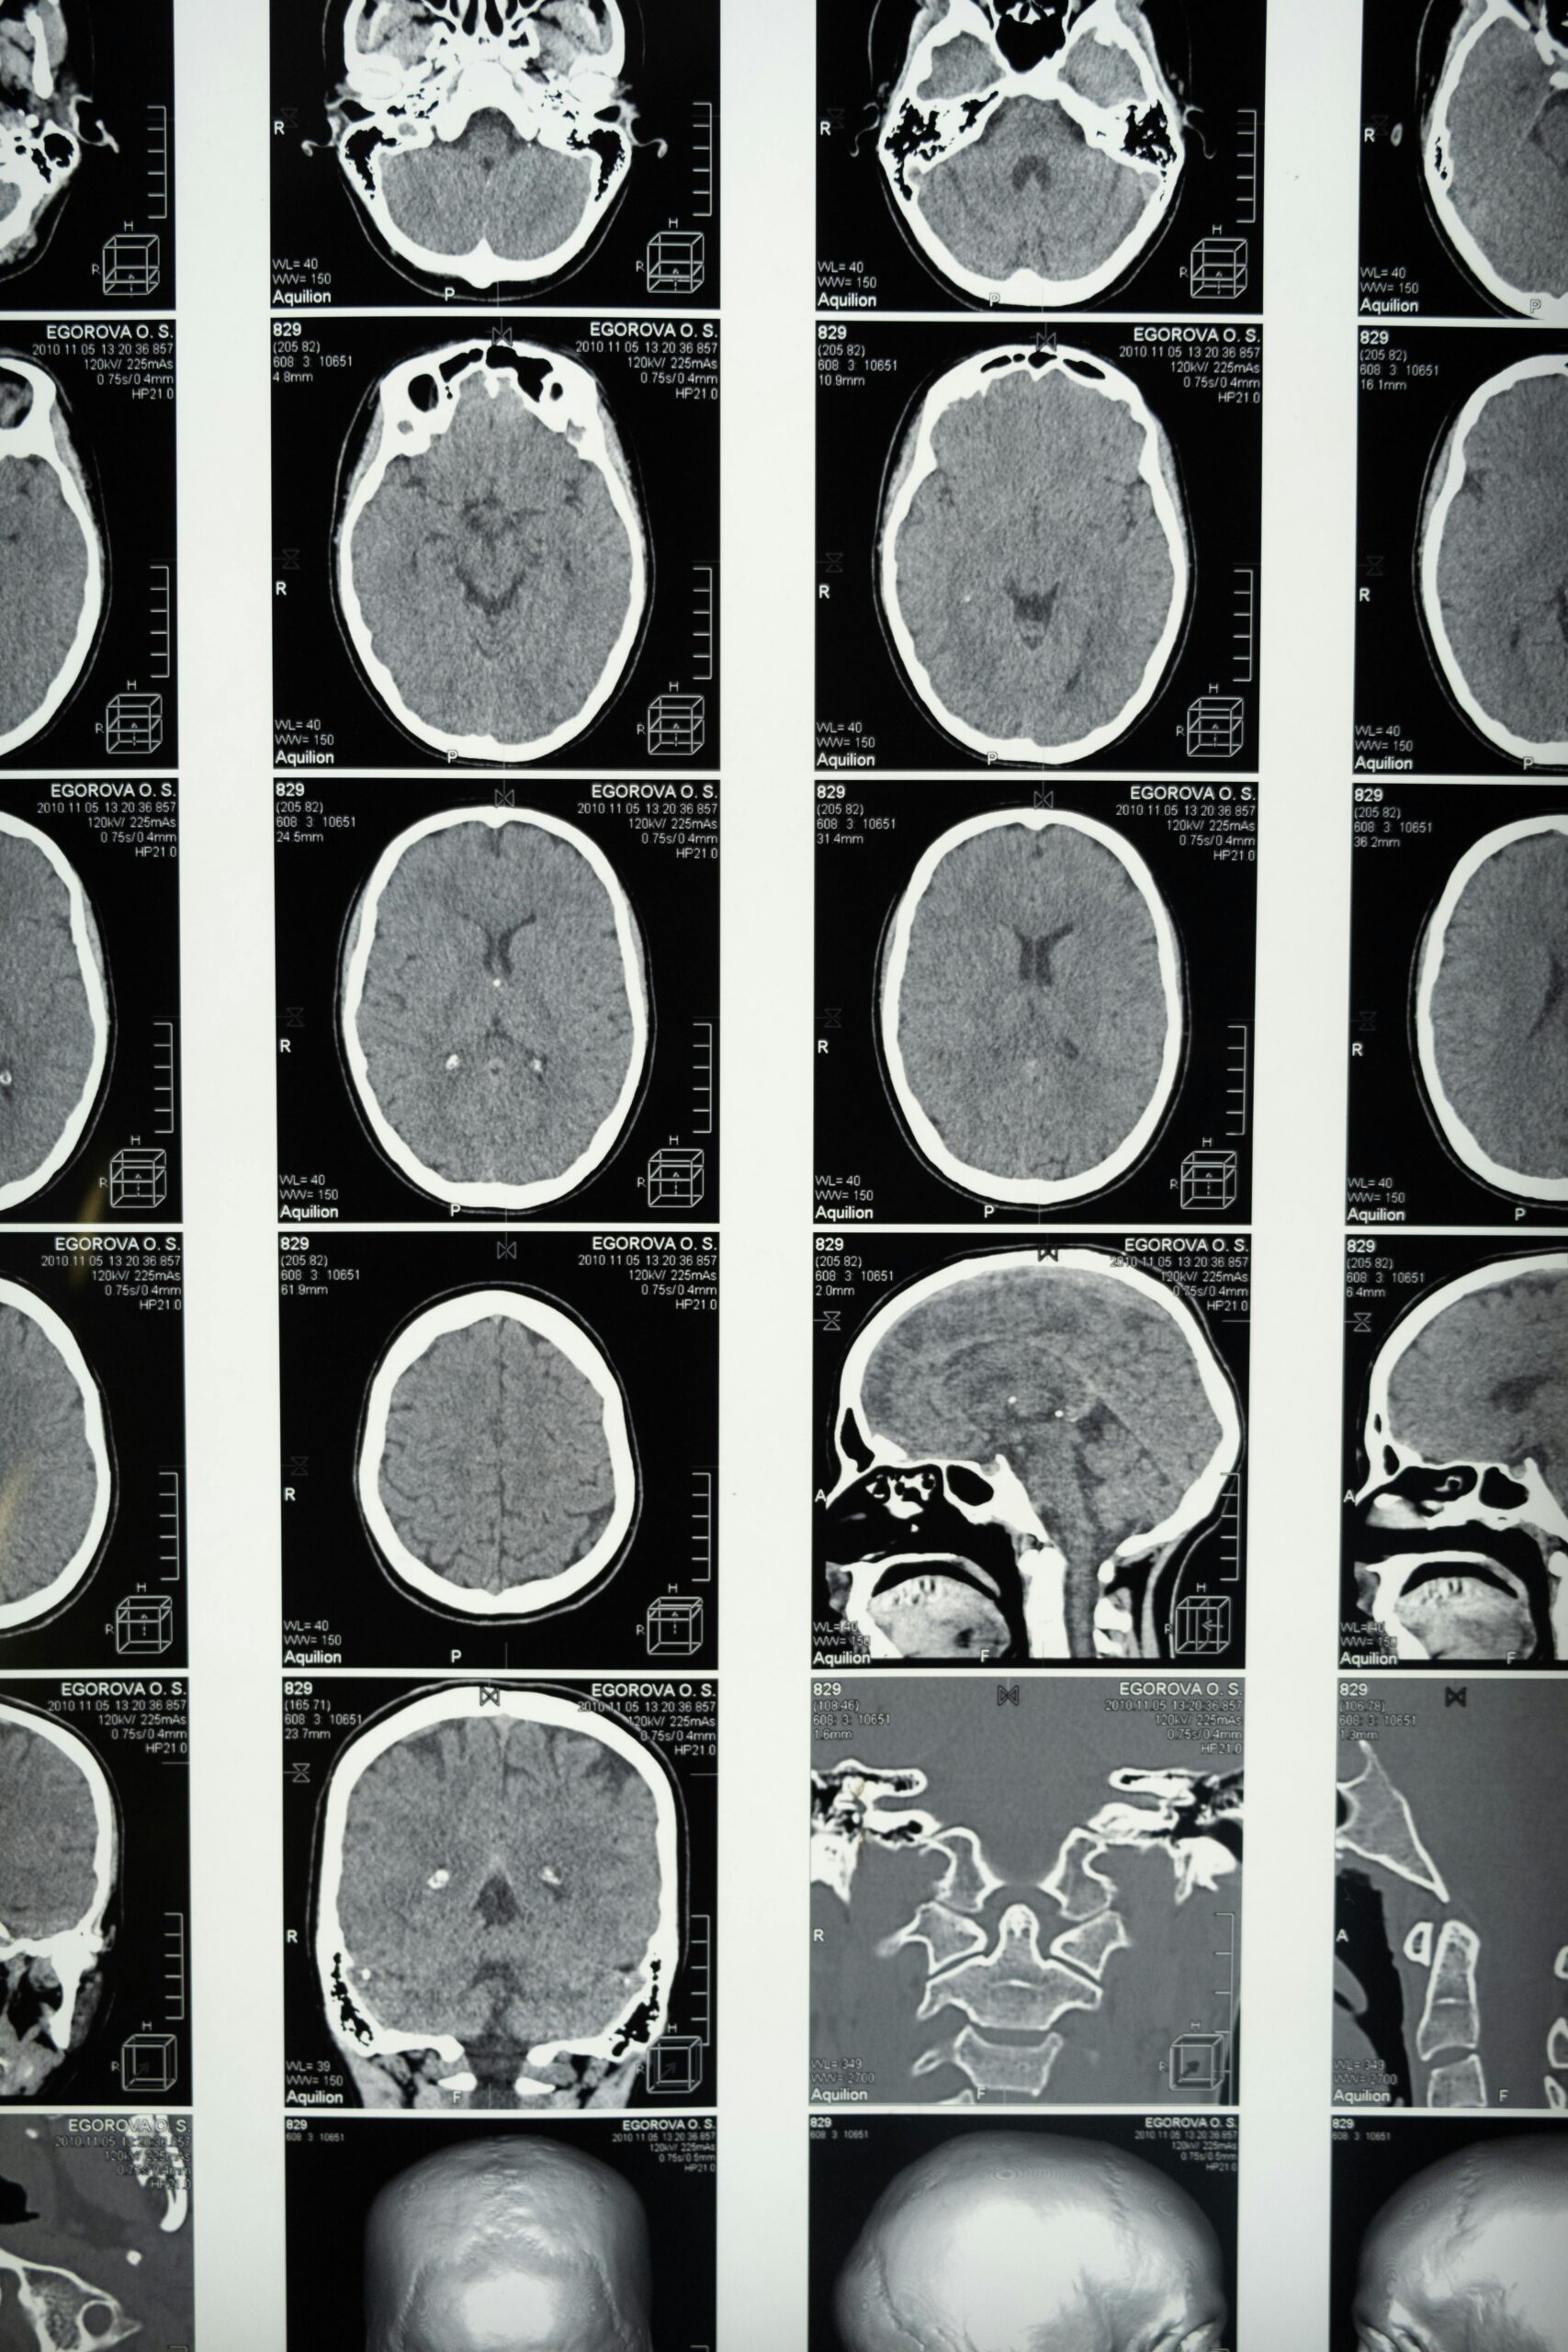

A recent New York Times investigative report by Mike McIntire describes how genetic and brain imaging data from thousands of U.S. children were used by a small group of researchers to advance a race science agenda. The data came from two large, federally funded studies—the Philadelphia Neurodevelopmental Cohort (PNC) and the Adolescent Brain Cognitive Development (ABCD) study—and were made available by the National Institutes of Health (NIH) to outside researchers in 2018 and 2020.